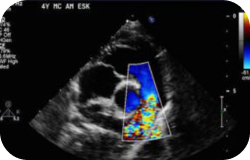

This test uses ultrasound to examine the heart’s chambers, valves, and blood flow. It helps detect the cause of chest pain, shortness of breath, irregular heartbeats, or an enlarged heart.

M-mode 2D echocardiography and cardiac doppler are performed to obtain views of the heart and look at how blood flows through the heart chambers, heart valves, and blood vessels. This test is used to look for the cause of abnormal heart sounds, an enlarged heart, unexplained chest pains, shortness of breath, or irregular heartbeats; check the thickness and movement of the heart wall; look at the heart valves and check how well they work; see how well an artificial heart valve is working; measure the size and shape of the heart’s chambers; check the ability of your heart chambers to pump blood; detect a disease that affects the heart muscle and the way it pumps; and look for blood clots and tumors inside the heart.